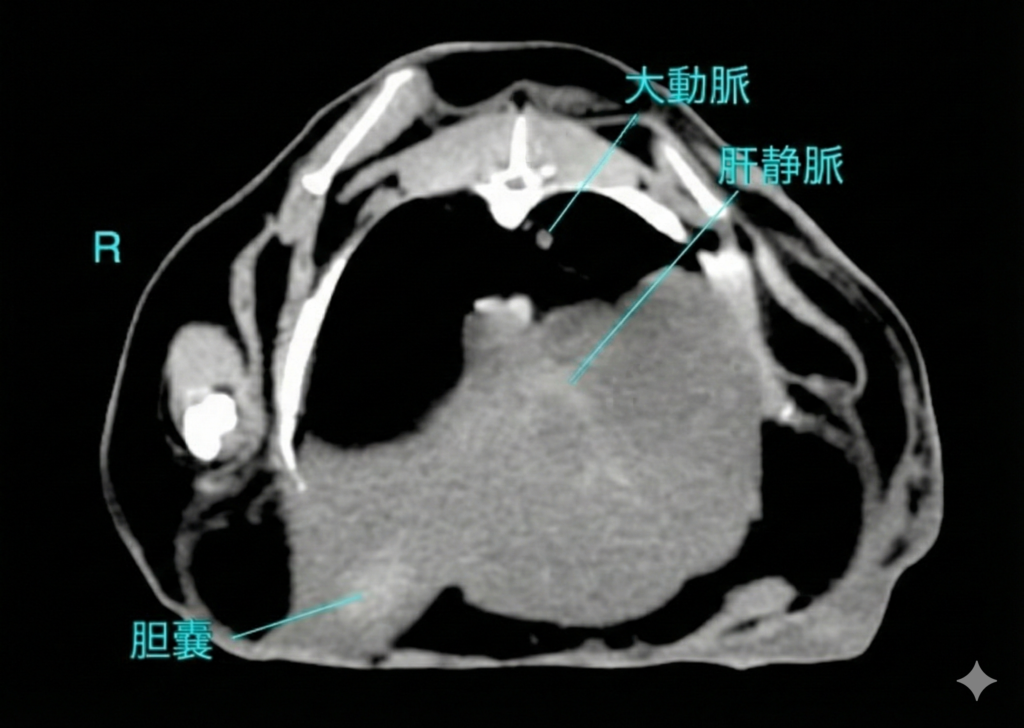

CT検査

CT検査は、X線吸収値(CT値)を用いて組織密度を絶対的な数値として評価できるため、脂肪肝の重症度判定において最も客観的かつ精度の高い非侵襲的検査法です。

CT値による診断

診断が不確定な場合や、腫瘍性疾患との鑑別が必要な場合にCT検査を実施します。脂肪のCT値は約-110HUであり、肝細胞内に脂肪が蓄積すると、肝実質全体のCT値が低下します。

正常肝のCT値

健康なウサギの肝臓の非造影CT値は、概ね45〜65HUの範囲にあります〔Kawata et al.1984〕。 正常な状態では、肝臓のCT値は脾臓のCT値と同等か、わずかに高いです。

脂肪肝のCT値

ウサギを用いた実験的脂肪肝モデルの研究により、肝臓のトリグリセリド含有量とCT値の間には強い負の相関があることが証明されています。 軽度脂肪肝では 正常値からの低下は軽微であり(数HUの低下)、視覚的な判定は困難な場合があります。中等度〜重度脂肪肝では肝臓のCT値が40HU未満 に低下した場合、脂肪肝と診断されるます。 重症例では0HUに近づき、さらに進行するとマイナス値(例:-15HUなど、脂肪組織に近い値)を示すこともあります。 脂肪乳剤の投与や治療介入による改善・悪化を、CT値の経時的変化(10~20HUの変動など)として定量的にモニタリングすることが可能です〔Kawata et al.1984〕。

造影CT検査の有用性と限界

脂肪含有量の定量評価には、造影剤の影響を受けない非造影CTの方が適しています。造影後は、血流動態や造影タイミングによってCT値が変動するため、脂肪評価の相関が弱くなるからです。 肝腫瘍や膿瘍、肝葉捻転の診断には造影撮影が不可欠です。特に肝葉捻転では、患部肝葉の造影効果欠損が明瞭に描出されるため、全体的に造影される脂肪肝との鑑別が可能となります。